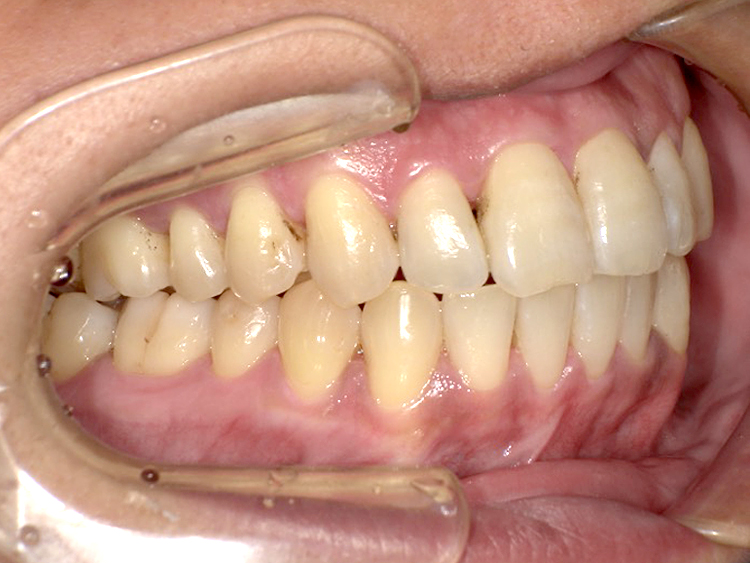

症例4

Before

After

| 主訴 | 上下前歯のがたつき |

|---|---|

| 年齢 | --- |

| 治療 期間 |

約9ヶ月 |

| 治療 内容 |

インビザラインiGoで上下顎の治療。 |

| 治療費 | ¥550,000(税込)/調整料含む |

| 治療のリスク | 矯正終了後は、リテーナーを指示通りに使用し、歯の後戻りを防ぐ必要があります。 |